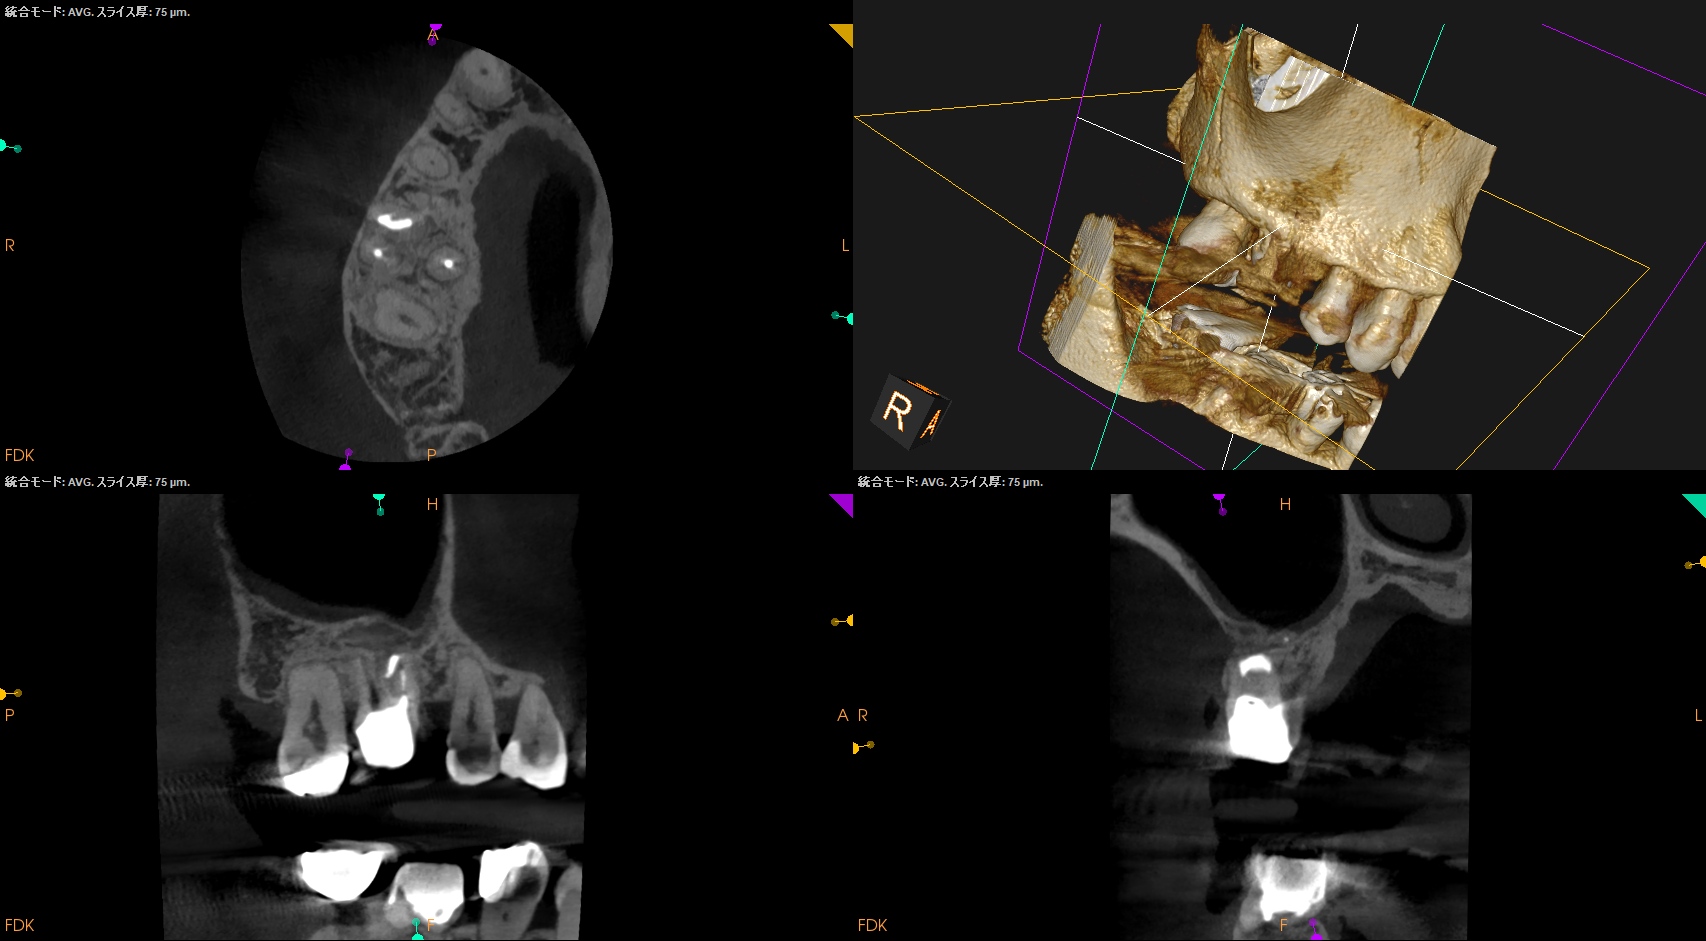

MB,DBのApicoectomyは

MB

CEJよりも12mm下方にMBのApexがあり、

そこを3mm切断するには6.4mmの切断幅が必要である。

そしてMB1-MB2を往復でPrepする必要があり、やや煩雑だ。

中程度の難易度だろう。

DB

DBはCEJよりも10.5mm下方にApexがあり、そこを3mmで切断するには5mmの頬舌的幅が必要で1根管なことからここはEasyだ。

術後にPA, CBCTを撮影した。

B

問題はないだろう。

#3 MB, DB Apicoectomy 7M recall(2026.3.30)

P

7ヶ月前と比較した。

劇的に歯槽骨の開創は回復している。

そしてP根だが、根尖病変の治癒とともに口蓋側の骨欠損が大きく回復しているのがわかる。